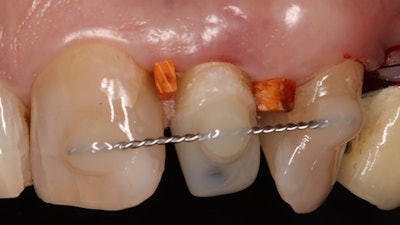

A wire splint affixed to the treated tooth.

Prior to the extrusion, patients underwent sufficient endodontic obturation and treatment or retreatment of the fractured tooth. Then, an AES was used to conduct a forced surgical extrusion of a fractured tooth to its required length. It was immediately fixed by two interdental wedges, and, afterward, the anchor screw of the extraction system could be removed, the authors wrote.

Titanium posts were airborne-particle abraded with aluminum oxide particles, and the dentin was etched for 10 seconds with 37% phosphoric acid. An adhesive core buildup was conducted with composite, and a wire splint or composite fixation was affixed to the adjacent teeth in the coronal/supragingival position, the authors wrote.